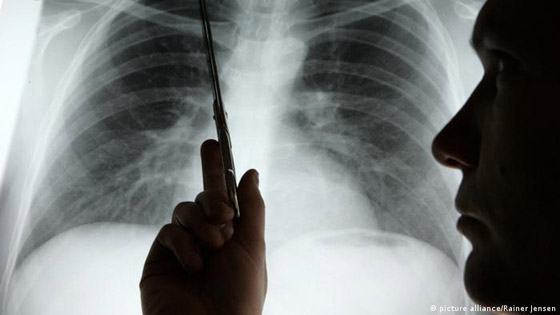

انتبهوا.. أعراض سهلة الملاحظة تنذر بسرطان الرئة

حذر أطباء متخصصون من أن تورم الوجه قد يكون علامة رئيسية على الإصابة بسرطان الرئة. يحدث تورم الوجه عندما يضغط الورم على الوريد الأجوف العلوي (SVC)، الذي يربط الرأس بالقلب، إذ يشير الأطباء إلى أن أغلب حالات انسداد الوريد الأجوف العلوي (SVCO) ناتجة عن سرطان الرئة.

ولفت الأطباء إلى أن معظم حالات انسداد الوريد الأجوف العلوي ناتجة عن سرطان الرئة أو انتشار المرض إلى الغدد الليمفاوية القريبة، بحيث تصبح منتفخة.

كما كشف الخبراء بالمجال أنه بالإضافة إلى تورم الوجه، قد يحصل تورم في الرقبة والذراعين وأعلى الصدر بسبب ضغط الوريد. كما تشمل الأعراض المصاحبة الأخرى ضيق التنفس أو الصداع أو تغيرات في البصر، أو ظهور أوردة زرقاء على الصدر أو الدوخة. وسرطان الرئة نادر الحدوث لدى من تقل أعمارهم عن 40 عاما، ويؤثر في الغالب على كبار السن.

ودعا أطباء إلى الإقلاع عن التدخين فورا كونه السبب الرئيسي، حيث تشير إحصائيات علمية إلى أن المدخنين يتصدرون الإصابة بهذا المرض بنسبة 70% من الإصابات.